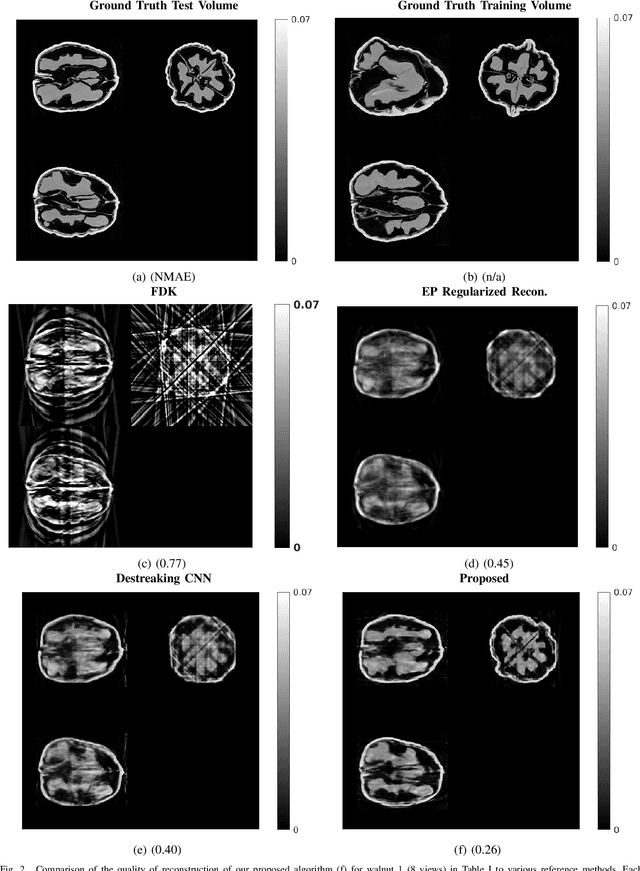

Abstract:Reconstruction of CT images from a limited set of projections through an object is important in several applications ranging from medical imaging to industrial settings. As the number of available projections decreases, traditional reconstruction techniques such as the FDK algorithm and model-based iterative reconstruction methods perform poorly. Recently, data-driven methods such as deep learning-based reconstruction have garnered a lot of attention in applications because they yield better performance when enough training data is available. However, even these methods have their limitations when there is a scarcity of available training data. This work focuses on image reconstruction in such settings, i.e., when both the number of available CT projections and the training data is extremely limited. We adopt a sequential reconstruction approach over several stages using an adversarially trained shallow network for 'destreaking' followed by a data-consistency update in each stage. To deal with the challenge of limited data, we use image subvolumes to train our method, and patch aggregation during testing. To deal with the computational challenge of learning on 3D datasets for 3D reconstruction, we use a hybrid 3D-to-2D mapping network for the 'destreaking' part. Comparisons to other methods over several test examples indicate that the proposed method has much potential, when both the number of projections and available training data are highly limited.